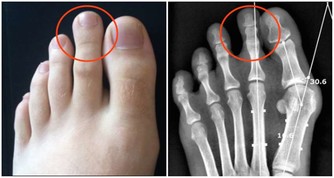

2.中老年人膝蓋疼是欠抽

在大會現場,《大河健康報》記者的左膝髕骨軟化,打過幾次封閉,至今上樓、爬山甚為不便。趙之心老師說:

「20多歲的年輕人就髕骨軟化?這是60歲以上的老人才會有的病。你給我靠牆罰站去。」

1保膝蓋靠罰站,打封閉不好使

趙之心是這樣讓記者罰站的:背部靠牆站好,雙腿下蹲,作「小半蹲」訓練。

記者堅持了一兩分鐘,休息30秒接著「蹲」,記者在從蹲姿到站立時,膝關節明顯有力了。趙之心說:

「膝關節有問題,打封閉是不好使的。這就像你天天喝自來水,突然一天喝不幹凈的河水,打了封閉,髒東西進去,再也休想清理乾淨。只有運動才能刺激關節液的產生。」

「這個動作我能堅持看完一場足球賽,你每天練上20~40分鐘,一個月治不好你的病,我請你去北京吃大餐。」